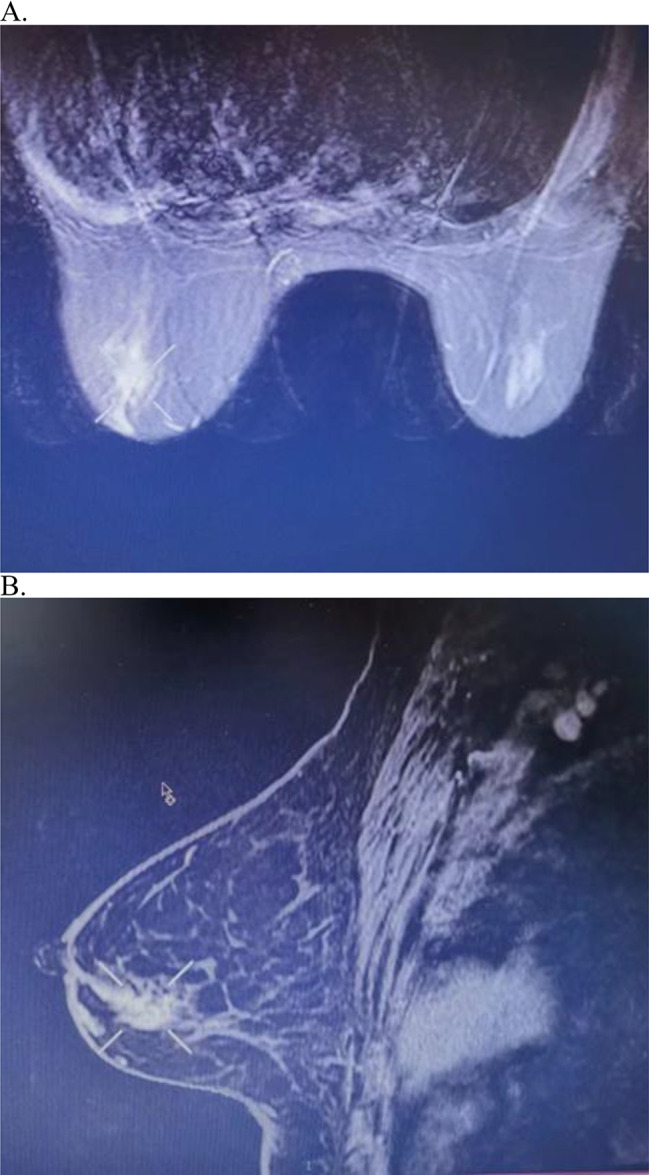

Given the rarity of RAD51C mutations, the risk and treatment of metachronous breast cancer after the diagnosis of ovarian cancer in RAD51C mutation carriers is not clear, especially for those who have received PARPi treatment. We report the case of a 65-year-old woman diagnosed with stage IIIC high-grade serous primary fallopian tube cancer. The patient had no family history of breast or ovarian cancer. The patient received three cycles of neoadjuvant chemotherapy with paclitaxel and carboplatin and achieved a complete response. After interval debulking surgery, the patient received three cycles of adjuvant chemotherapy. Collection and extraction of saliva DNA for next-generation sequencing identified a RAD51C mutation c.838-2 A > G. The patient received niraparib as front-line maintenance treatment. After 36 months of niraparib treatment, the patient had grade II invasive ductal carcinoma of the left breast that was positive for estrogen receptor (90%) and Ki-67 (30%) and negative for progesterone receptor and human epidermal growth factor receptor 2. Computed tomography revealed the absence of distant metastases. Modified radical mastectomy and axillary lymph node dissection were then performed. The final pathological report of the breast showed a 1.8 cm Bloom-Richardson grade II invasive ductal carcinoma in the left breast with axillary lymph node metastasis (1/21). Finally, the breast cancer was stage IIA, pT1cN1M0. The metachronous breast cancer in this case may be the first report of second primary cancer in fallopian tube cancer patient harboring a RAD51C mutation during niraparib treatment. Further studies are required to determine optimal treatment.